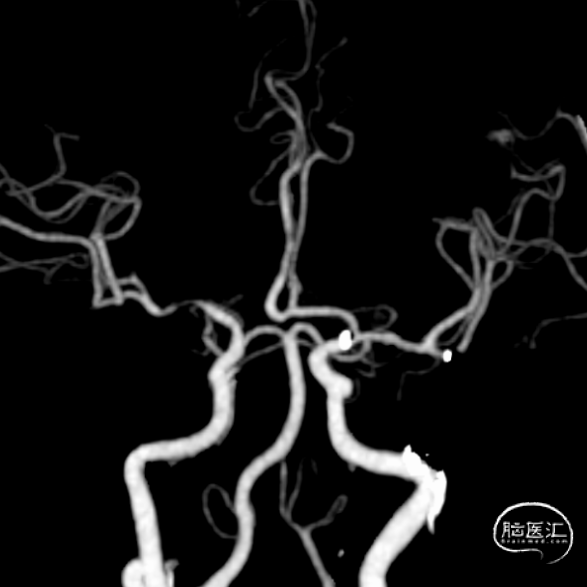

术后复查CTA:提示左侧大脑中动脉通畅,支架在位。

最后路径手推造影,造影确认脑血流完全恢复,mTICI 3级。

考虑狭窄明显并夹层形成,遂行4.5*22mm 自膨式闭环支架于左侧大脑中动脉水平段并造影。